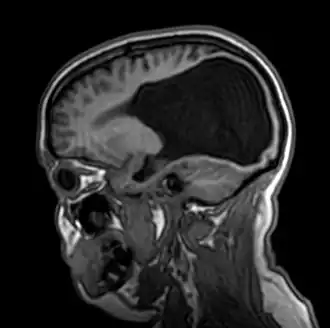

![]() Resonancia magnética en un plano sagital de la cabeza | ||

La colpocefalia es un trastorno en el cual se evidencia un crecimiento anormal de las astas occipitales —la porción posterior de los ventrículos laterales (las cavidades o compartimientos) del cerebro—. Este crecimiento anormal sucede cuando ocurre un subdesarrollo o una falta de espesamiento en la materia blanca del cerebro posterior. La microcefalia (cabeza anormalmente pequeña) y el retraso mental son característicos de una colpocefalia. Otras condiciones incluyen anormalidades motrices, espasmos musculares y convulsiones.